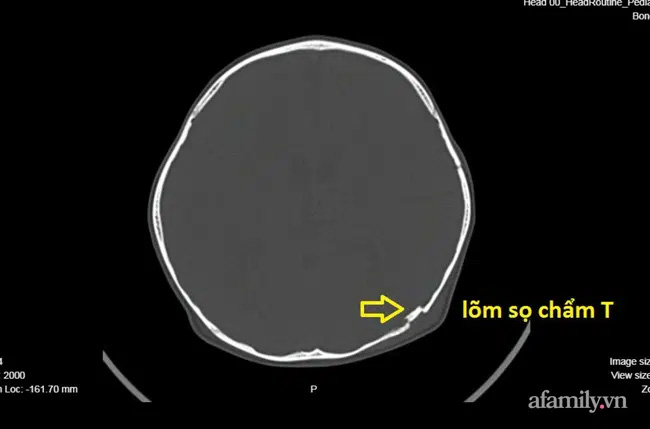

Qua thăm khám lâm sàng, kết quả chụp CT ghi nhận B. bị lõm sọ kín vùng chẩm trái. Một mảnh xương nhỏ lõm vào não cần phải được phẫu thuật khẩn cấp để nâng bản sọ lõm.

Ảnh chụp cho thấy bé bị lõm vùng sọ trái. (ẢNh: BVCC)